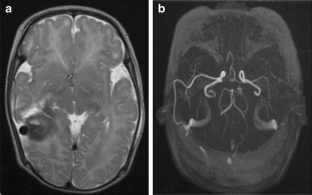

Intracranial pial arteriovenous fistulas (AVF) are rare vascular malformation especially in the first 2 years of life. The pathology in this age group is associated with greater morbidity and mortality. We report a rare case of 36-day-old male infant with a pial AVF associated with an arterial aneurysm, who presented with intraventricular hemorrhage and hydrocephalus. In addition, an online review of the literatures on pediatric pial AVF was performed using PubMed on published case reports and articles from 1980 to April 2013.

Fig. 1